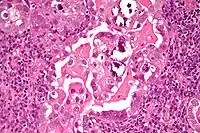

Histology H&E of uterine serous papillary carcinoma. H&E stain.

Micrograph of uterine serous carcinoma demonstrating characteristic psammoma bodies and cilia. H&E stain.

Characteristic discohesiveness of cells (like falling apart) around fibrovascular cores

Histopathologically, uterine serous carcinomas is typically characterized by (1) nipple-shaped structures (papillae) with fibrovascular cores (2) marked nuclear atypia (irregularities in the nuclear membrane, enlarged nuclear size), (3) psammoma bodies and (4) cilia.